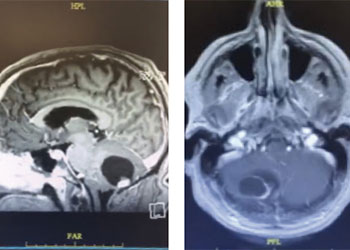

This is a 56-year-old man with a history of COPD and asthma who presented with a syncopal event and one week of retro-orbital headaches, blurry vision, and personality changes including apathy and disinhibition. He had a 40- pack-year smoking history but no prior malignancy. The exam revealed a pronator dri on the le upper extremity. MRI brain demonstrated 2 large right frontal heterogeneously enhancing masses with vasogenic edema causing midline shi and subfalcine herniation. The largest lesion was 3.9 x 4.0 cm on the inferior/sub frontal cortical surface, while the other was 3.0 x 2.7 cm in the superior subcortical frontal lobe. Further imaging showed a mediastinal mass suspicious for malignancy. He was started on Decadron for edema and Keppra for seizure prophylaxis.